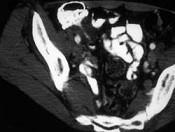

问题 男,42岁,右下腹痛、腹胀半年,无浅表淋巴结肿大,影像检查如图,最可能的诊断是 ( )

选项 A、肠结核 B、腹膜后纤维化 C、结肠癌 D、Crohn氏病 E、淋巴瘤

答案 D